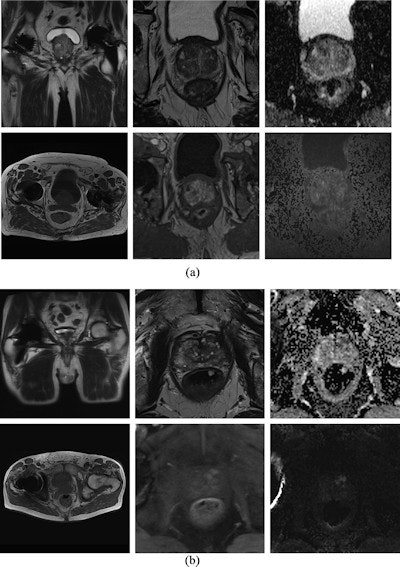

Diagnostic MRI at 1.5 tesla and 3 tesla. MpMRI without impairment of diagnostic value at 1.5 tesla (a) and 3 tesla (b). Top left shows localizer with little susceptibility artifacts caused by the total hip replacement. Top center: T2-weighted images. Top right: Apparent diffusion coefficient maps. Bottom left: T1-weighted images. Bottom center: T1 volumetric interpolated breath-hold examination (VIBE) for dynamic contrast-enhanced images. Bottom right: Diffusion-weighted imaging high b-values (b1800). Image courtesy of the European Journal of Radiology.

Diagnostic MRI at 1.5 tesla and 3 tesla. MpMRI without impairment of diagnostic value at 1.5 tesla (a) and 3 tesla (b). Top left shows localizer with little susceptibility artifacts caused by the total hip replacement. Top center: T2-weighted images. Top right: Apparent diffusion coefficient maps. Bottom left: T1-weighted images. Bottom center: T1 volumetric interpolated breath-hold examination (VIBE) for dynamic contrast-enhanced images. Bottom right: Diffusion-weighted imaging high b-values (b1800). Image courtesy of the European Journal of Radiology.MpMRI of the prostate has become a significant part in the detection and monitoring of prostate cancer, and the number of MRI examinations has increased significantly in the past decade. Meanwhile, total hip replacement is a common orthopedic operation in the developed world, with the rate predicted to double by 2035.

Artifacts due to total hip replacement can be severe enough to degrade MRI image quality and interfere with interpretation. Thus, effective imaging techniques to help limit image distortion and artifacts are essential, according to the authors.